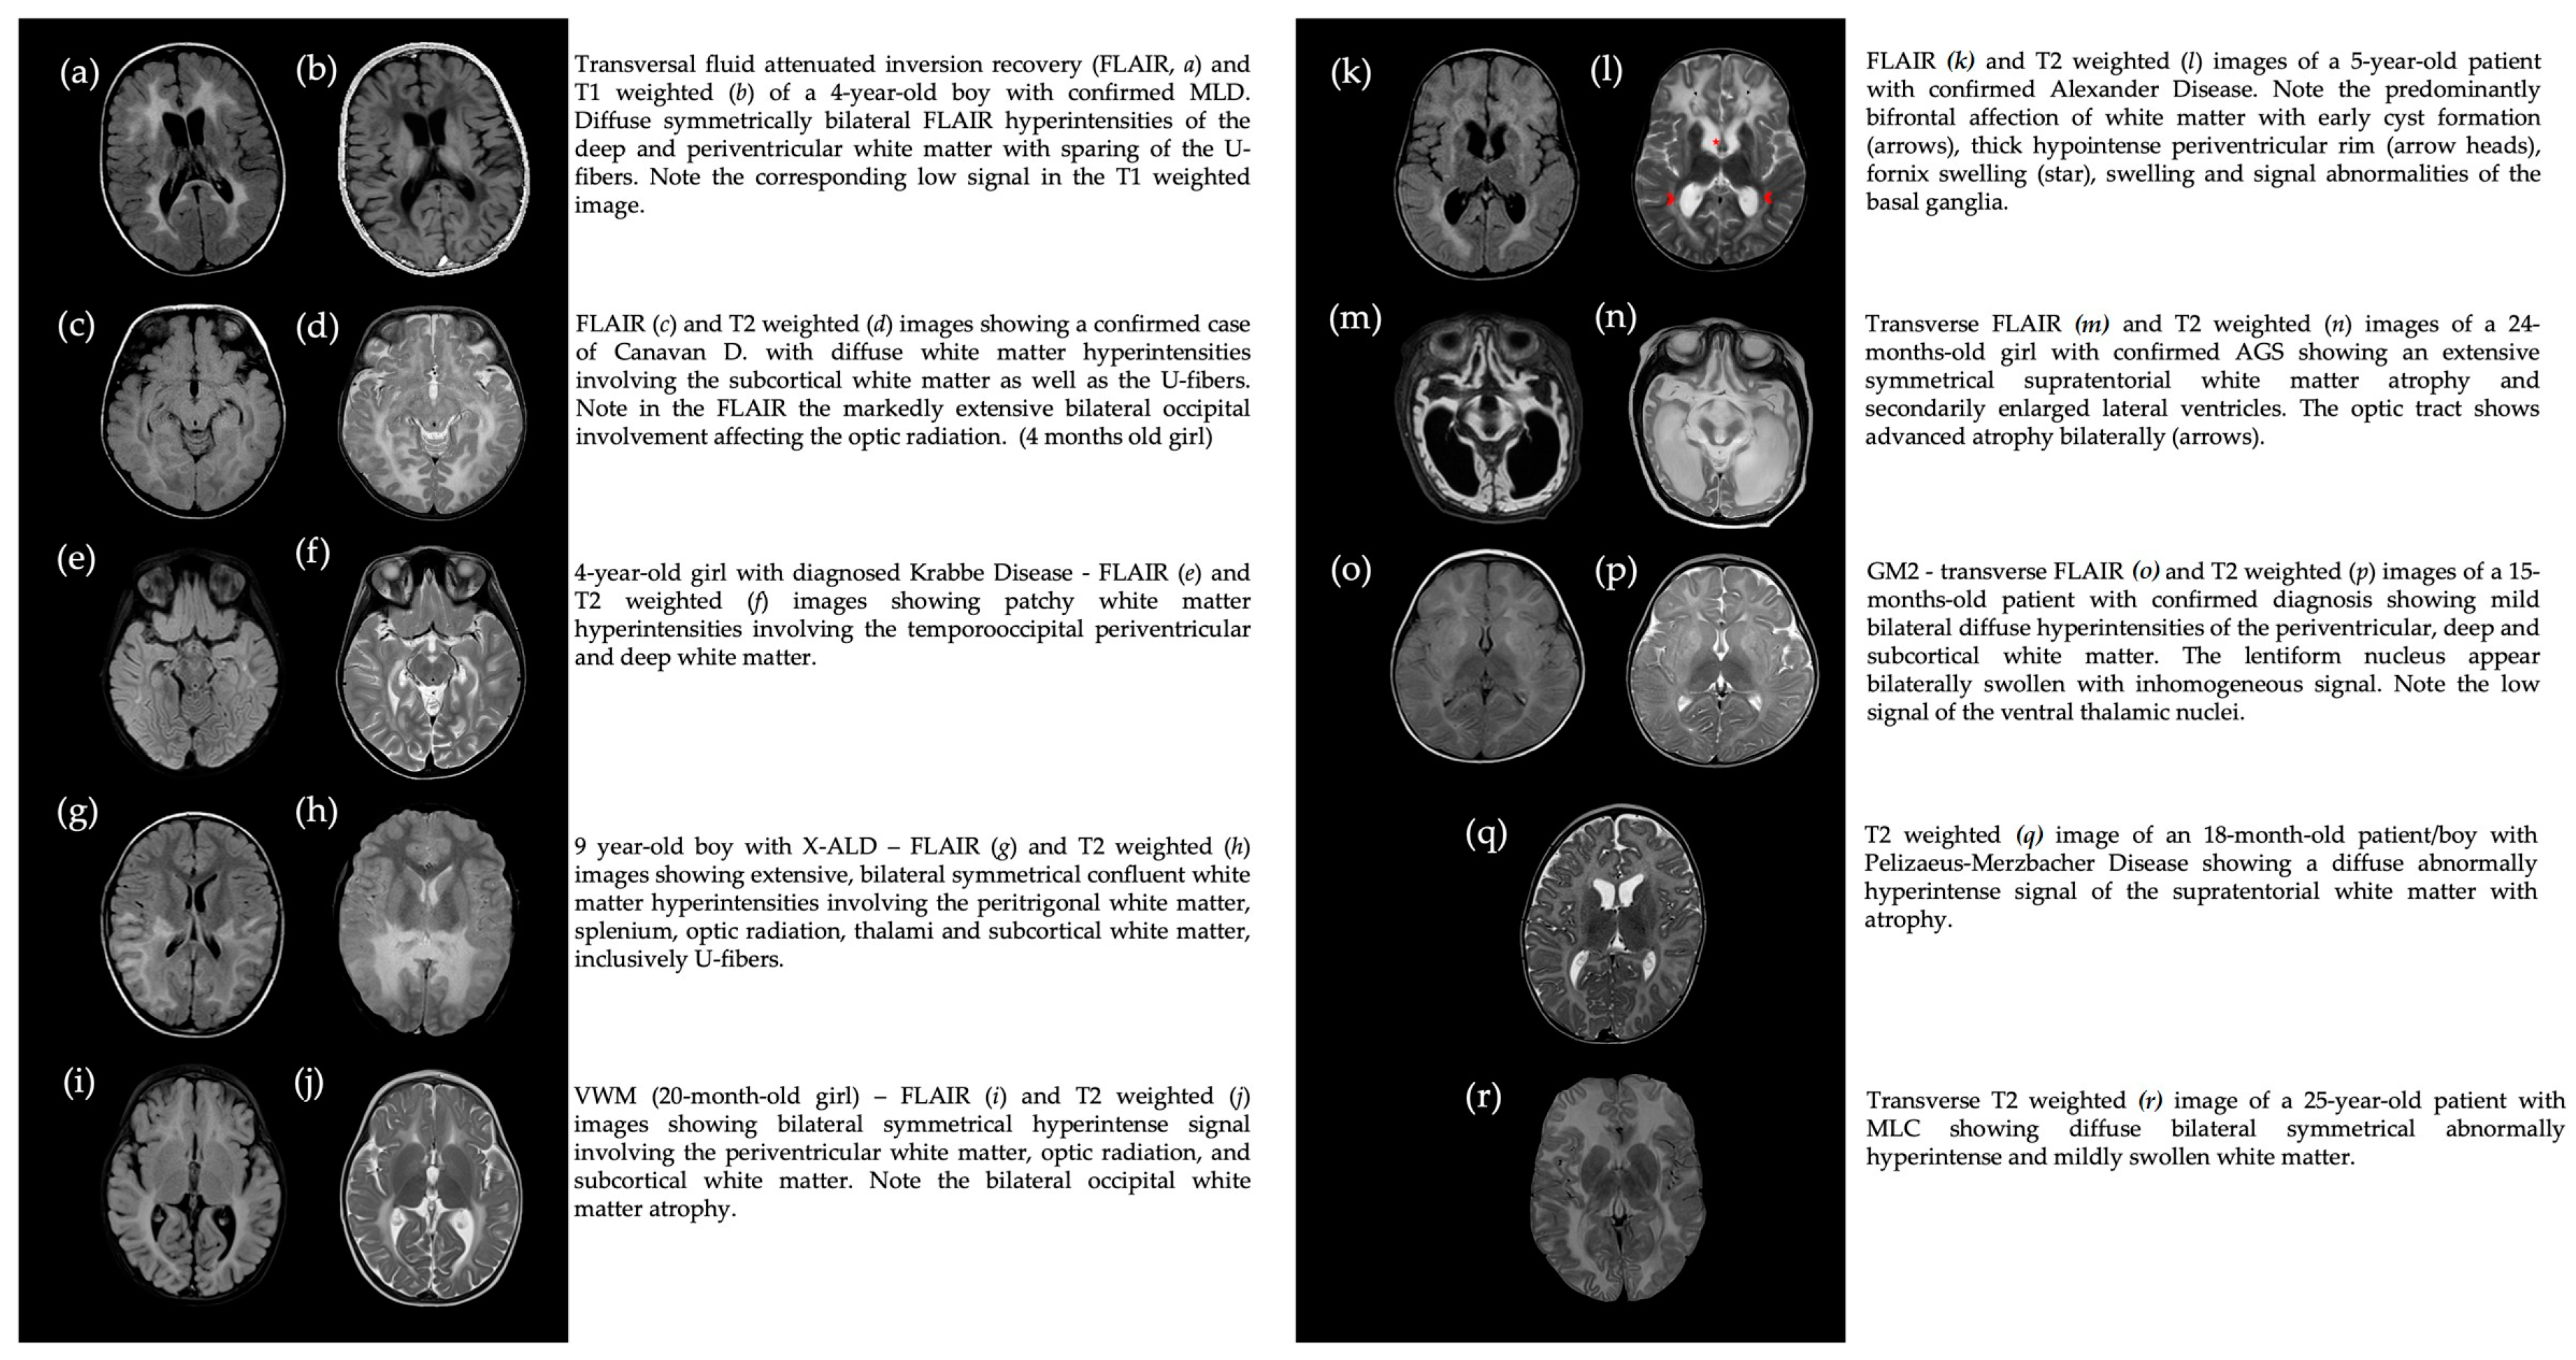

2.2. MRI Analysis

3.5. MRI Findings Correlate with Neuro-Ophthalmologic Findings